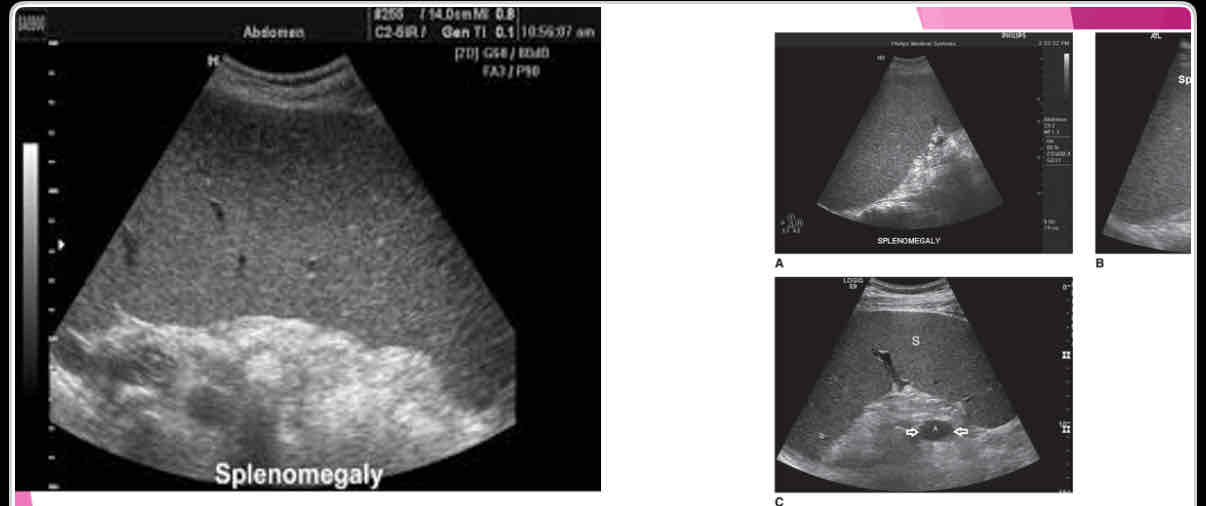

What is the measurement for enlarged spleen (splenomegaly)?

>13cm in length

What is the most common splenic abnormality observed sonographically?

enlargement (splenomegaly)

What is the most common cause of splenomegaly?

Portal hypertension due to cirrhosis is most common cause in adults

With splenomegaly: when enlarges, it extends

anteriorly, medially and inferiorly